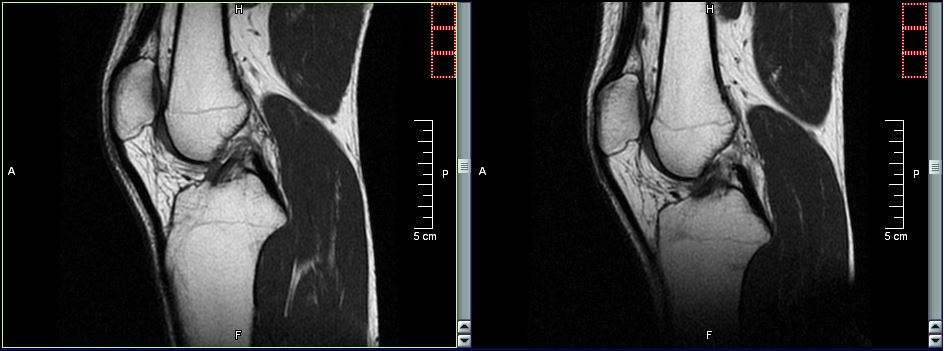

Dalle tue parole sembra che ti sia stata riscontrata una condropatia o sindrome femoro.rotulea, cioè una sofferenza cartilaginea nell'articolazione tra la faccia interna della rotula ed i condili femorali.

Sempre dalle tue parole sembra che la causa POTREBBE essere un disallineamento rotuleo (dico "potrebbe" perchè non si possono escludere a priori la coesistenza di concause...come una modalità esecutiva non corretta di alcuni movimenti, oppure una extrarotazione del piede, o un "crollo della volta plantare" con conseguente iperpronazione del piede, ecc.ecc.). Il disallineamento della rotula c'è, io ad occhio nudo non la vedo, ma fermo e in posizione eretta l'ortopeda l'ha visto.

La falda fluida rilevata, immagino, con una ecografia fa pensare ad un conseguente fenomeno infiammatorio. Esatto, proprio tramite ecografia è stato rilevato questo leggero versamento e diagnosticata l'infiammazione.